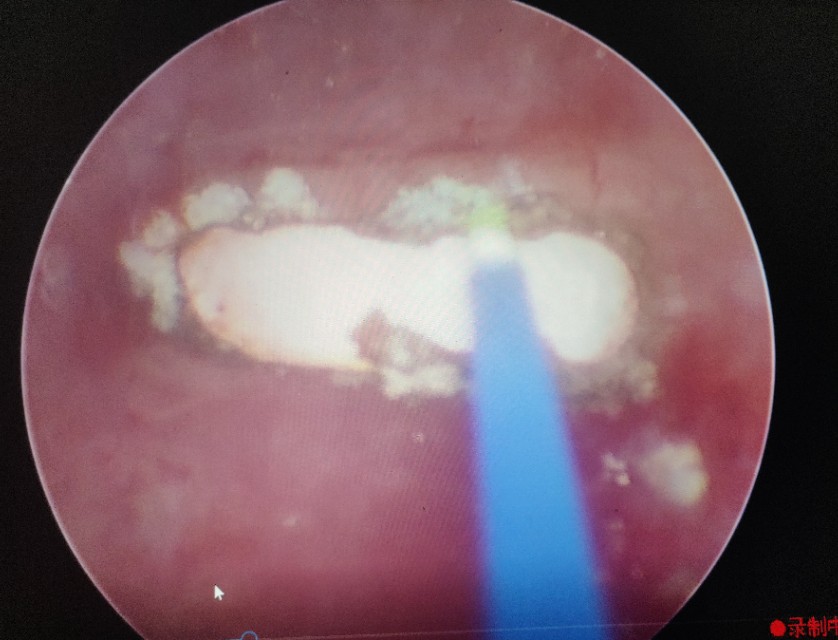

在手术室、麻醉科支持下手术开始,何晓北用钬激光一点点的将两枚结石击打成小碎块,随着结石的去除,节育环渐渐露出了真容,粉红色的两个端头丝毫不像能给患者带来剧烈腹痛的样子。何晓北用激光击打节育环的金属丝,靳永池带领的外一科团队紧盯着屏幕,做好了实施第二、三套方案的准备。随着几次亮光闪烁,节育环成功打断,接着从另一侧取出节育环剩余部分,去除碎石屑,手术顺利,成功结束。